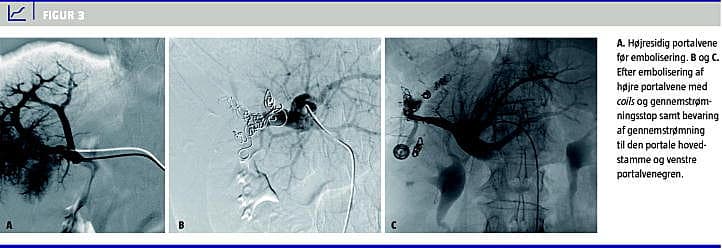

Ofte kan PVE gennemføres under sedering og i morfinrus med lokal analgesi på punkturstedet, men af og til vil generel anæstesi være nødvendig. Forud for indgrebet skal der foreligge normale trombocyttal og international normalized ratio inden for normalområdet. Adgang til portalvenesystemet foretages ved perkutan punktur under kombineret ultralyd- og røntgengennemlysningsvejledning (evt. CT-vejledning) og kateterisering af en central portalvenegren [12]. Oftest vil det dreje sig om højresidig PVE med eller uden embolisering af segment 4. Når adgangen til portalvenesystemet er etableret, indlægges en sheath og herigennem et kateter, og portalveneangiografi udføres i relevante projektioner (Figur 3 A). Emboliseringen foretages under røntgengennemlysningsvejledning. I princippet kan alle emboliseringsmaterialer anvendes, men det anbefales at anvende enten mikropartikler til embolisering af de perifere portalvenegrene efterfulgt af coils til proksimal embolisering (Figur 3 B + C) eller en blanding af n-butyl-cyanoacrylat (NBCA) og ioderet olie (lipoidol) [13-15]. Forskellige emboliseringsmaterialer til PVE har været evalueret i griseforsøg. NBCA og 50-150 mikrometer polyvinylalkoholpartikler blev fundet at give signifikant bedre embolisering og fibrosering ved patologisk undersøgelse end de øvrige testede emboliseringsmaterialer [15]. Andre har beskrevet god klinisk succes med anvendelse af vascular plugs med lav morbiditet og god vækst af FLR [16]. Temporært virkende emboliseringsmateriale som spongostan resulterer i dårligere hypertrofi end brug af permanente emboliseringsmaterialer, og ingen emboliseringsmaterialer har udvist hepatotoksicitet i dyreforsøg [17].

Efter proceduren foretages fornyet angiografi for at bekræfte minimal gennemstrømning eller gennemstrømningsstop i de relevante venegrene og fortsat bevaret gennemstrømning i den raske FLR (Figur 3 B + C). Der bør bevares en tilstrækkelig lang portalvenebifurkatur, til at kirurgisk afklemning og ligering af højre portalvene er mulig sidenhen (Figur 3 C). Den intraparenkymale hepatiske stikkanal kan under fjernelse af sheath 'en emboliseres med spongostan og/eller coils. Efter PVE observeres patienten for blødning de efterfølgende seks timer.